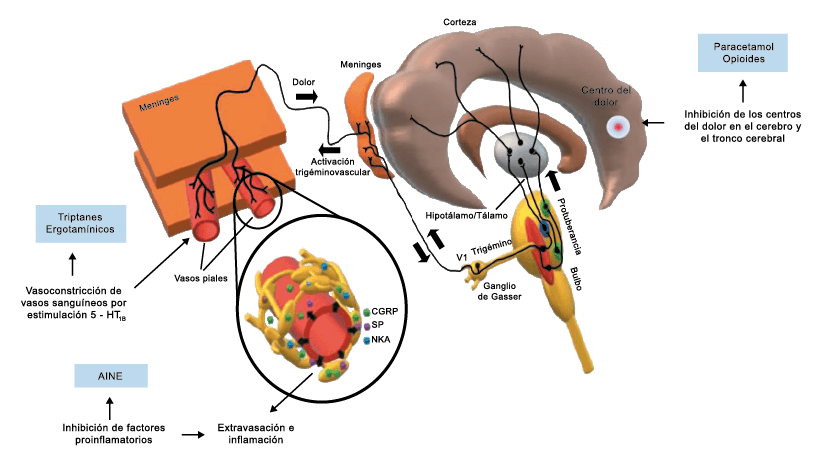

Posteriormente diversos estudios demostraron que la infusión de 5-HT podría abortar tanto la cefalea inducida por reserpina(55) como la espontánea(56). En respuesta a estos estudios, el sistema del receptor 5-HT ganó mucha atención, lo que culminó con el descubrimiento de los triptanos, la serotonina y los agonistas del receptor 5-HT1B/1D(57). Todos exceptuando el 5-HT3 (canal iónico controlado por ligando) son receptores acoplados a proteína G. Si bien los triptanos se clasifican como agonistas de los receptores 5-HT1B/1D, la mayoría también activa en menor medida los receptores 5-HT1A, 5-HT1E o 5-HT1F(58). Originalmente, los triptanos se desarrollaron para actuar sobre la vasculatura craneal, una idea apoyada por sus claras acciones vasoconstrictoras(59) (Figura 25) y la expresión preferencial del receptor 5-HT1B en los vasos craneales más que en los periféricos(60).

Un mecanismo neural de los triptanos en las terminaciones del nervio trigémino periférico podría inhibir la liberación de neuropéptidos proinflamatorios y la vasodilatación dural neurogénica(63), lo cual era consistente con el tema en desarrollo de la migraña como una enfermedad neurovascular. (Figuras 26 y 27)

En la figura 28 se muestra un resumen de los fármacos y sus mecanismos de acción en el contexto del sistema trigémino vascular.

A pesar de la clara farmacología de los triptanos en el tratamiento de la migraña, su uso es limitado en pacientes con factores de riesgo cardíaco(61), lo que obliga a dirigirse a receptores que carecen de acción vasoconstrictora. Una de esas dianas es el receptor 5-HT1F, que es activado hasta cierto punto por algunos triptanos, como el naratriptán y no por otros, como el rizatriptán(62). (Tabla 2)

La toxina botulínica tipo A (BT-A) fue descrita por primera vez por Binder y colaboradores en 1991 como tratamiento preventivo para la migraña al observar que cuando pretendían reducir líneas de expresión faciales en algunos pacientes estos vieron como también se redujeron los dolores de cabeza por migrañas. La BT-A ya ha sido utilizada previamente como tratamiento de otras afecciones tales como hiperhidrosis axilar, estrabismo, acalasia o alteraciones musculares como distonías y espasticidad. La inyección vía subcutánea de toxina botulínica tipo A (BT-A) en el cuero cabelludo, fue aprobada en 2011 por la FDA. Diversos estudios in vitro e in vivo han demostrado que la TBA inhibe la liberación de la sustancia P y de aminoácidos excitadores y péptido relacionado con el gen de la calcitonina) (Figura 29). Más recientemente, su efecto antinociceptivo ha sido relacionado con inhibición de liberación de glutamato (Figura 30).